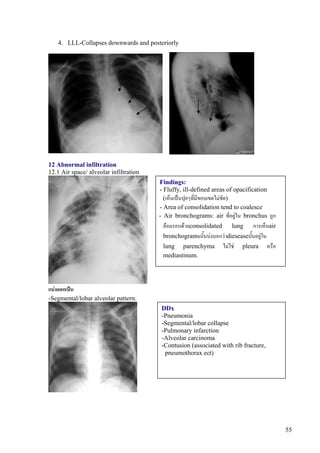

12 Abnormal infiltration

12.1 Air space/ alveolar infiltration

Findings:

- Fluffy, ill-defined areas of opacification

(เห็นเปนปุยๆที่มีขอบเขตไมชัด)

- Area of consolidation tend to coalesce

- Air bronchograms: air ที่อยูใน bronchus ถูก

ลอมรอบดวยconsolidated lung การเห็นair

bronchogramsนั้นบงบอกวาdieseaseนั้นอยูใน

lung parenchyma ไมใช pleura หรือ

mediastinum.

แบงออกเปน

-Segmental/lobar alveolar pattern:

DDx

-Pneumonia

-Segmental/lobar collapse

-Pulmonary infarction

-Alveolar carcinoma

-Contusion (associated with rib fracture,

pneumothorax ect)